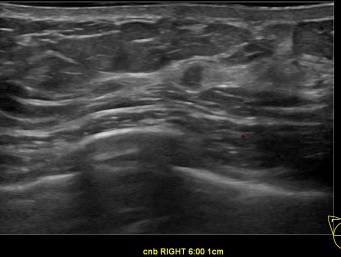

상기환자는 만져지는 멍울과 유두분비물로 내원하신 70대

여성분으로 의심스러운 우측혹 조직검사 시행해 유방암으로 진단되었습니다